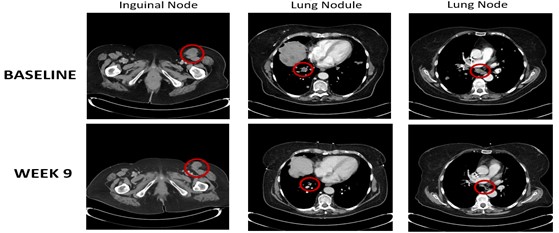

|

● |

A PR was observed in a patient with metastatic melanoma who was previously treated with nivolumab and progressed on nivolumab. Below is a series of CT scan images from this patient. The patient had multiple metastases at baseline and reached a PR based on a 38% decline in linear tumor burden at week nine. This PR was confirmed at week 17. |

A PR was observed in a patient with metastatic melanoma of mucosal origin who was previously treated with first-line regimen of ipilimumab plus nivolumab followed by second-line nivolumab as a monotherapy. After progressing on the prior regimens, the patient had joined the trial with multiple metastases at baseline. This patient reached a PR based on a 58% decline in linear tumor burden at week 17. This PR was not confirmed. |